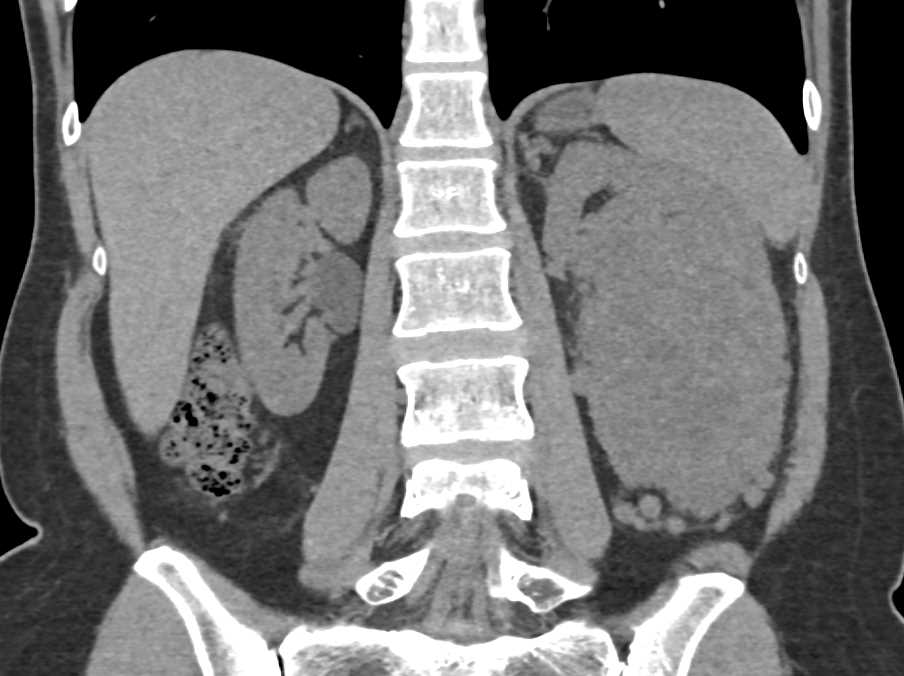

Renal Cell Carcinoma with Neovascularity